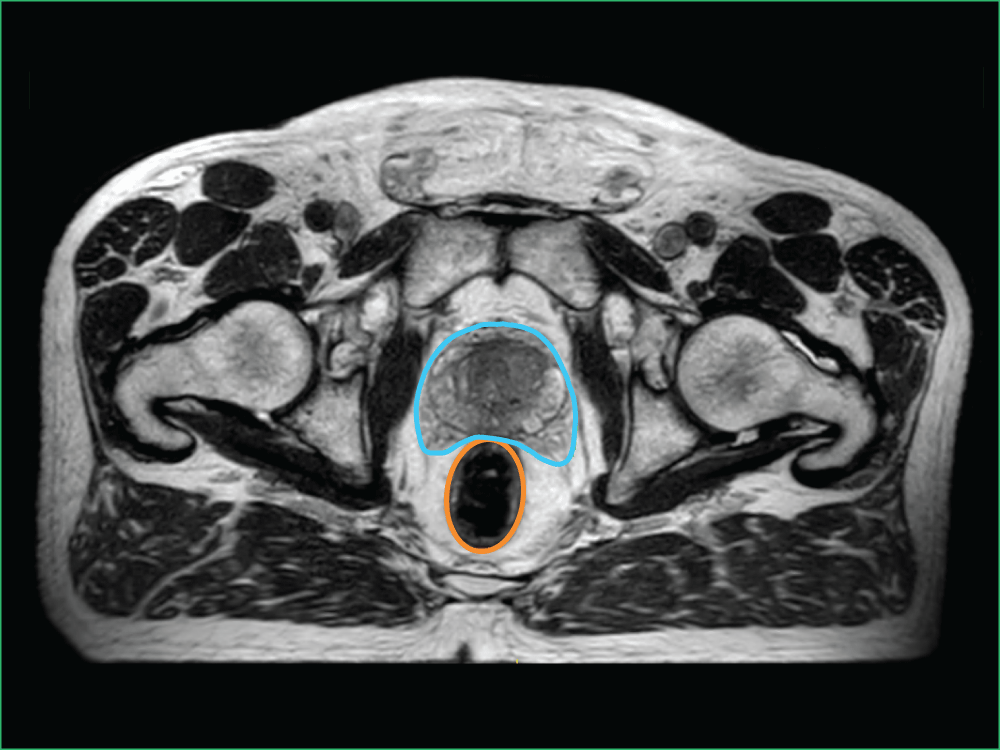

Image B shows the high level of detail available with MRI-guided radiation therapy. You can see the:

- Planned target volume outlined in blue

- Bowel outlined in orange

Image A: Bottom view

Image B: Clinical imaging scan